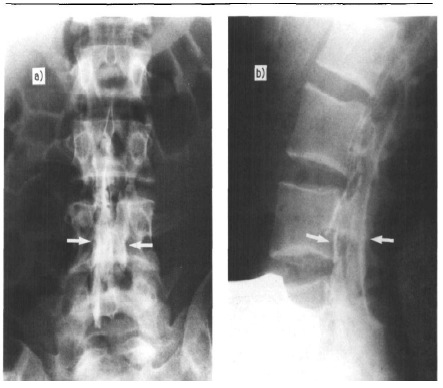

Il s’agit d’une jeune parturiente de 26 ans, primipare, pesant 70 kg pour 160 cm. Elle n’a aucun antécédent particulier et est classée ASA 1 au terme de la consultation pré-anesthésique. Une analgésie péridurale dans le cadre du travail obstétrical est réalisée après consentement éclairé. La ponction a été faite au niveau de l’espace intervertébral L2-L3 en position assise. L’espace péridural (EP) a été identifié sans problème par la technique de la perte de résistance franche au mandrin liquide. La distance « peau-espace péridural » est de 4,5cm et le cathéter est monté à 3 cm au-delà de cette distance. Aucun reflux spontané ou par aspiration à la seringue n’a été remarqué. Une dose test de Lidocaïne deux pour cent avec adrénaline 1 : 200 000 n’a produit aucun effet anesthésique ou cardiovasculaire après 5 minutes. Elle reçoit un bolus de 9 mL de Ropivacaïne 0,2% avec 5 μg de Sufentanil. L’entretien se fait par analgésie péridurale contrôlée par la patiente (APCP). La solution analgésique utilisée est le mélange Ropivacaïne 0,15% et Sufentanil 0,5μg/mL. Le débit de base est de 5 mL/h, le bolus étant de 5 mL avec une période réfractaire de 12 minutes. La dose maximum horaire est de 60 mg d’anesthésique local (AL).Le bolus initial a provoqué une anesthésie sensitive morcelée : paresthésie des membres inférieurs, de la région claviculaire gauche et du membre supérieur gauche à prédominance radiale. Par ailleurs, on note un syndrome de Claude Bernard-Horner gauche associé à une érythrose de l’hémiface homolatérale. Ces symptômes sont apparus 35 minutes après administration du bolus initial et ont complètement disparu à la 6è heure. La tension artérielle, la fréquence cardiaque, la respiration et l’état de conscience sont restés parfaitement stables et normaux. Le bloc moteur était modéré.L’accouchement s’était déroulé dans ces conditions et était eutocique. Après la délivrance et avec l’accord de la parturiente, nous avons pu localiser le cathéter avec l’injection de produit de contraste hydrosoluble (10 mL d’Omnipaque® 180). Les clichés de face (Figure n°1 a) et de profil (Figure n°1 b) démontrent que le produit s’est accumulé sans équivoque dans l’espace sous-dural

Sur le cliché de face : opacification partielle du fourreau dural en regard de L3-L5. L’absence de mise en évidence des racines de la queue de cheval permet pratiquement d’exclure une injection sous-arachnoïdienne. Sur le cliché de profil on observe une image en double rail dans le canal rachidien, en positions antérieure et postérieure par rapport au sac dural, signalant la localisation sous-durale du produit de contraste.